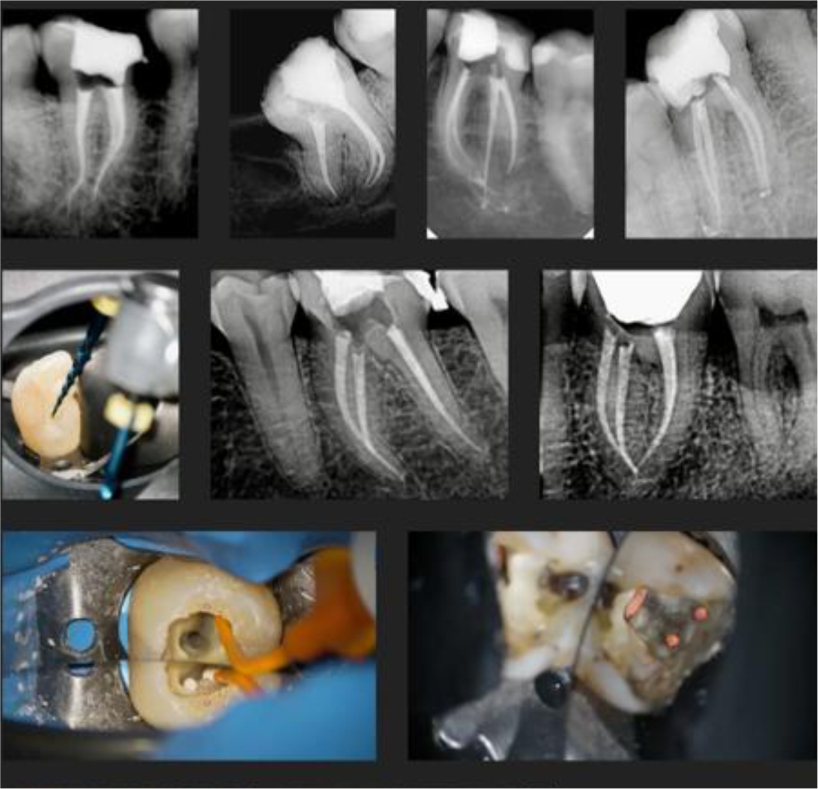

Преди няколко месеца започнах да работя с RECIPROC® blue. Бях приятно изненадан от неговата гъвкавост и пластичност, както и неговата висока издръжливост на циклична умора и ниско съпротивление на огъване, което намалява възможността от счупване в случаите с по-изразени изкривявания.

RECIPROC® blue е в състояние да промени структурното си поведение при температура и стрес, променящи се от аустенитна фаза към мартензитна фаза, да стане по-пластичен и по-добре се адаптира към канала когато напрежението се увеличи. Това е голямо предимство в сравнение с конкуренцията. По мое мнение, най-голямото предимство за използването на RECIPROC® blue е, че изоставяме използването на набор от механични инструменти и спокойно можем да използваме само един. Приложеното налягане трябва обаче да бъде по-ниско, тъй като този нов инструмент се държи различно.

RECIPROC® blue е отличен вариант за използване в случаите, когато достъпът е много ограничен, защото има предимството да може да претърпи деформация без риск от счупване. Освен това може също да се използва за преминаване през обструкции или камъни. Естествено, вашата конкретна техника винаги зависи от кореновия канал, който лекувате.

В повечето случаи използвам директно RECIPROC® blue до средната трета и след това C-PILOT за глисадата и ендодонтска дължина. Тази техника позволява лечение в 70-80% от случаите. В останалите ситуации използвам различни подходи, докато не създам път, който ми позволява да използвам RECIPROC® blue.